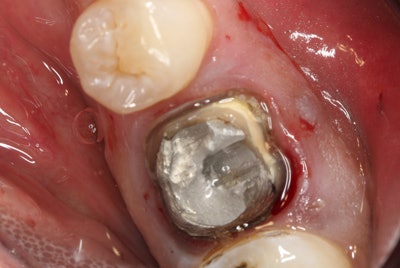

The patient in this case presented with a nonrestorable, root canal-treated mandibular molar tooth (figures 1-3). After patient consultation, it was decided that the tooth would be extracted and grafted in preparation for a dental implant.

Since the roots were divergent and it was a mandibular molar tooth where the bone is more dense, the treatment plan included the following:

- The crown would be removed.

- The tooth would then be sectioned and extracted as individual roots.

- The site would then be grafted with a simple technique in preparation for a future dental implant.